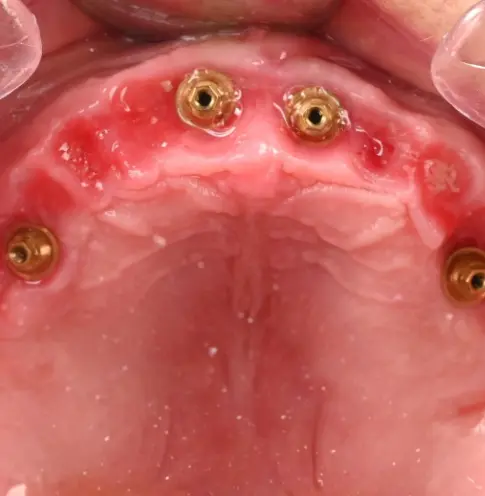

Dysfonction occlusale et esthétique avec inflammation gingivale, usure dentaire marquée et axes implantaires défavorables au maxillaire, compromettant une réhabilitation prothétique transvissée sans correction d’angulation.